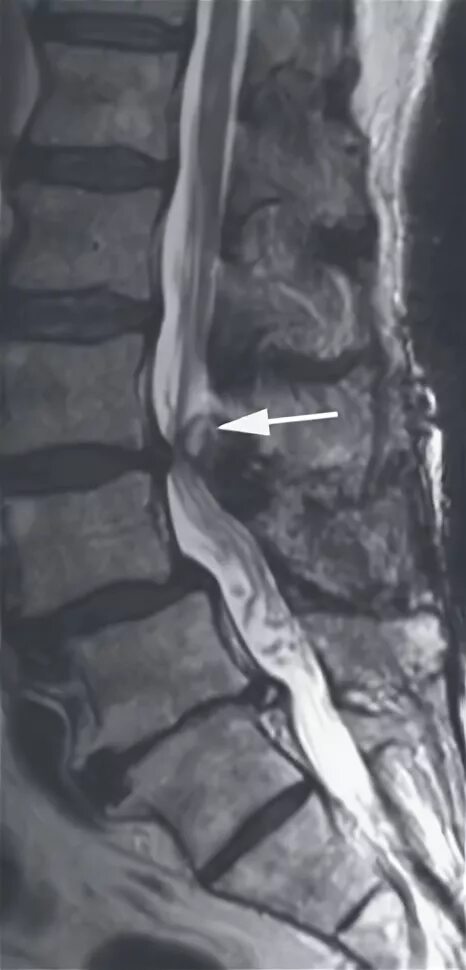

Спондилоартроз кт